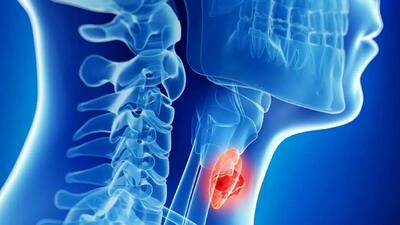

رکنا: فتق نافی یک وضعیت شایع است که به بیرون زدگی بافت یا اعضای داخلی بدن از طریق ناحیه ضعیف دیواره شکم اطراف ناف گفته میشود. این مشکل معمولاً در نوزادان و کودکان دیده میشود، اما در بزرگسالان نیز ممکن است رخ دهد و در بسیاری از موارد نیاز به درمان جراحی پیدا میکند.

بیماریهای خودایمنی زمانی ایجاد میشوند که سیستم ایمنی بدن که قرار است با مهاجمان بیرونی مبارزه کند، به اشتباه به بافتهای سالم خود بدن حملهور میشود. این حملات اشتباهی میتوانند التهاب، آسیب و اختلال در عملکرد انواع ارگانها و سیستمها ایجاد کنند.